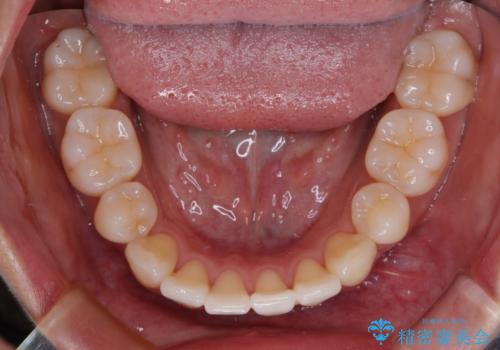

1. 抜歯矯正の軽度後戻りを解消 インビザライン矯正の治療前

2.

3. 抜歯矯正の軽度後戻りを解消 インビザライン矯正の治療後